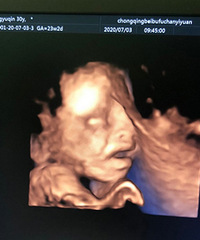

被个人娃儿的四维照片吓到了

1个月前 收录

阅读:2.3万回复:127